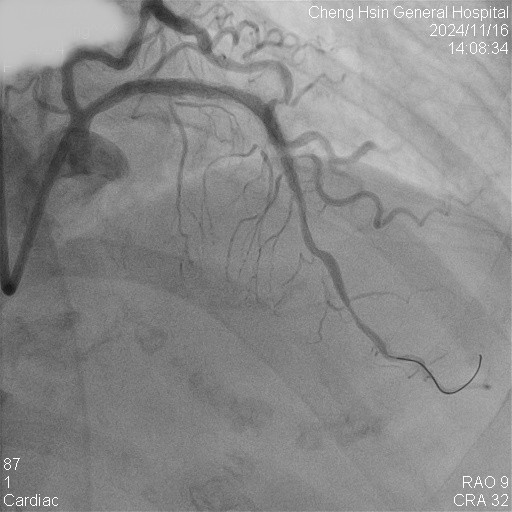

Initially, we tried to insert IVUS catheter but unable to cross the lesion. We tried a NC balloon but unable to cross it also.Hence, we used rotational atherectomy with 1.5mm burr. However, the burr was unable to cross lesion even in high speed and entrapped in the stent.We removed the burr in guide extension catheter then the NC balloon could cross the lesion. The IVUS cather could also cross it with guide extension catheter support. The stent was almost not expanded. We tried NC balloon high pressure dilation but balloon slippage and burst. The lesion was still un-dilatable. We insert cutting balloon which avoided slippage but remained burst. We escalated the burr size to 1.75mm. The larger burr was not stucked but still unable to cross lesion. Besides, the larger burr causing slow blood flow. After adenosine injection, the patient's blood flow recovered. We reduced the burred size to 1.25mm which cross the lesion once but entrapped while doing polishment. After burr retrieval, we used NC balloon high pressure dilation. The balloon bursted but the lesion remained un-dilatable.Finally, the lithotrypsy balloon could cross the lesion and eliminate 80 pulses. The lesion was expanded much well. The IVUS showed the old stent was expanded and calcium was cracked. We deployed a new stent for old one destruction and proximal dissection. The final IVUS image showed epansion and apposition were accpetable.

Case Summary